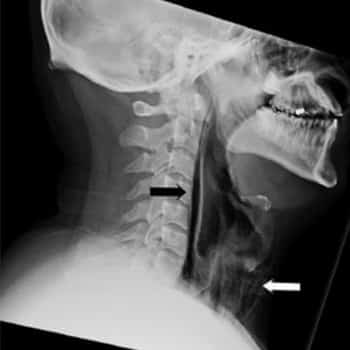

Entonces, los médicos analizaron la región hinchada y pudieron oír chasquidos. Realizaron una radiografía para saber lo que había por dentro de aquella hinchazón en el cuello y tuvieron una sorpresa: todo el espacio debajo de su barbilla estaba ocupado por el aire de los estornudos que aguantaba, como puedes observar en la imagen arriba, donde apunta la flecha blanca.